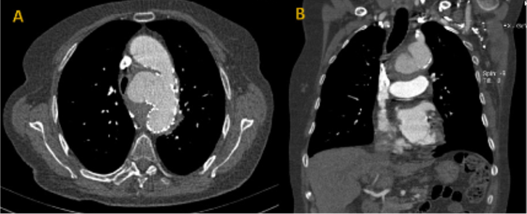

At admission, the patient was normotensive but tachycardic, and referred chest pain with pleuritic characteristics. Laboratory findings showed a normocytic normochromic anaemia with 11g/dl of haemoglobin, normal white blood count and elevated C reactive protein of 151 mg/l. Computed tomography angiography (CTA) was ordered revealing an aneurysmal dilation of the lesser curvature of the aortic arch with a maximum diameter of 65mm, Figure 2. Despite having no clear signs of rupture, or apparent recurrence of aortobronchial fistula, the rapid growth of the aortic arch aneurysm and its saccular morphology prompted the urgent treatment. The patient was submitted to urgent TEVAR with proximal sealing in zone 2 of the arch using a LifeTech® Ankura™ stent-graft. With the patient under general anaesthesia and anticoagulated with 70mg/kg of unfractionated heparin, a percutaneous access was made on the common femoral artery (CFA) of both groins; a 5-French introducer was placed on the right CFA, and after pre-closure using the Abbot’s® Prostar™ XL on the left CFA, the 24-French delivery system was advanced and the thoracic stent graft (LifeTech® Ankura™ TAA4238B160) was deployed proximally in zone 2 of the aortic arch.

Figure 2 Pre-operative axial (A) and coronal (B) computed tomography angiography image of aneurysm of the aortic arch with loss of proximal seal of the previously implanted stent graft.